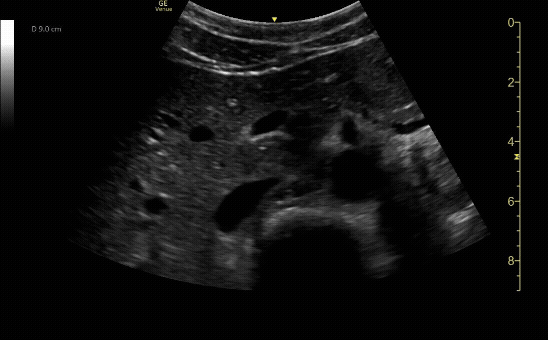

Aorta in transverse (short) view with intramural thrombus.

c/o Alejandro Ruiz, MD